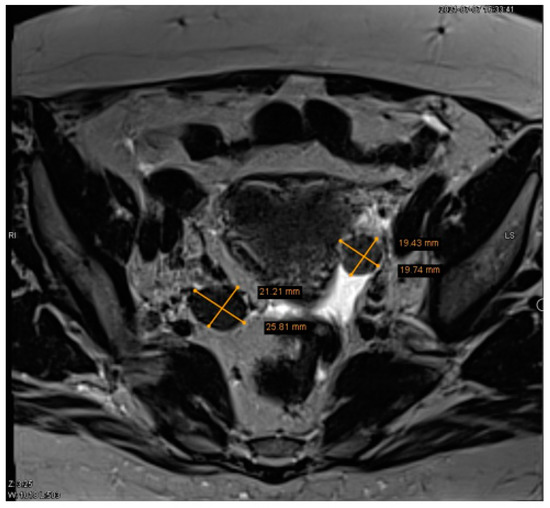

A 65-year-old Caucasian female (parity 2, abortions 1, and miscarriages 0) presented to an endocrinologist due to excessive body hairiness and alopecia. Over the past year she experienced these symptoms, which caused the patient significant psychological distress. The patient experienced menopause at age 55 years. She had a history of hysteroscopic polypectomy and other concomitant diseases, including primary hypertension, neurosensorial hearing loss, non-toxic multinodular goiter, obesity, detected multiple cystic lesions in the pancreas, characteristic of intraductal papillary mucinous neoplasm (IPMN), as well as bilateral parapelvic renal cysts. A Pap smear was performed several years ago, but the patient did not know the results. Laboratory testing showed increased levels of serum testosterone and dehydroepiandrosterone sulfate: total testosterone 25.96 nmol/L (normal range, 0.43–1.24), dehydroepiandrosterone sulfate (DHEA-S) 6.25 µmol/L (normal range, 0.8–4.9). Transvaginal ultrasound revealed the presence of two tumors in both ovaries, with the right measuring 3.1 × 2.8 cm and the left measuring 4.0 × 2.7 cm (Figure 1a,b).

Figure 1. (a) Transvaginal ultrasound of a 3.1 × 2.8 cm lesion in the right ovary. (b) Transvaginal ultrasound of a 4.0 × 2.7 cm lesion in the left ovary.